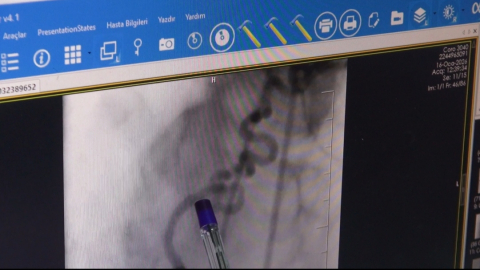

Batman’da yaşayan Şükrü Demirtaş, göğsünde yanma ve nefes darlığı şikayetiyle Batman Eğitim ve Araştırma Hastanesi Kardiyoloji Servisi’ne başvurdu. Yapılan anjiyoda kalbin sağ ana arterinden (RCA) köken alan ve akciğere uzanan anormal bir damar tespit edildi. Kardiyoloji Uzmanı Dr. Abdulaziz Taş ile Girişimsel Radyoloji Uzmanı Dr. Abdurrezzak Teken tarafından yapılan değerlendirmede, söz konusu damarın kalbe gitmesi gereken kanın bir kısmını ‘çalarak’ akciğere yönlendirdiği ve bu nedenle hastada göğüs ağrısı ile nefes darlığına yol açtığı belirlendi. Literatürde nadir görülen koroner çalma (steal) sendromu tanısı konulan hastaya işlem yapılması kararı alındı. Endovasküler yöntemle gerçekleştirilen embolizasyon işlemiyle, kalpten çıkıp akciğere uzanan ve kanı yönlendiren anormal damar başarıyla kapatıldı. İşlem sonrası hastanın şikayetlerinde belirgin düzelme sağlandı. Bu uygulamanın Batman’da ilk kez gerçekleştirildiği belirtildi.